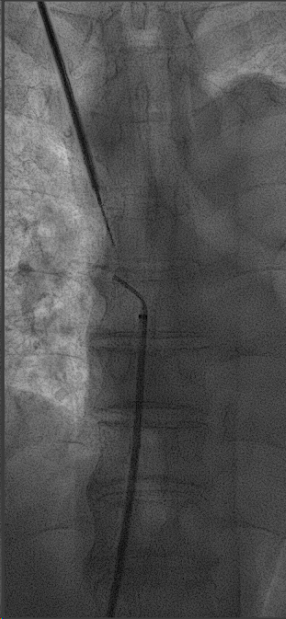

崔天蕾教授湍东运用经颈静脉肝内穿刺器械RUPS和房间隔穿刺针等多种手术器械,凭借精湛的技术和严谨的操作,克服了心脏搏动带来的干扰,成功在狭窄的穿刺区域中精确穿刺右心房,实现了上腔静脉闭塞处的导管再次植入。手术历时1小时10分钟,术后患者透析顺利,术后第三天出院。目前经过2个月的门诊随访,未见手术并发症及其他不适,该手术不仅为赵阿姨解决了透析通路的问题,也为血管通路的发展提供了新的思路和方法。

经右侧颈部鞘管,RUPS和房间隔穿刺针进行右心房穿刺